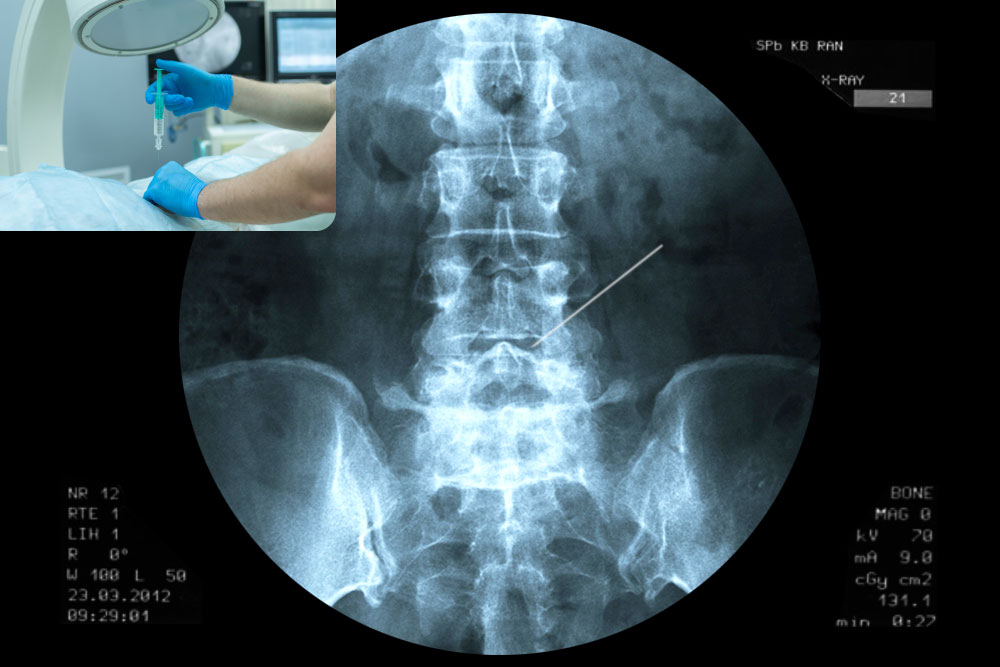

Рентгеновские технологии: усиленные экраны 35x35